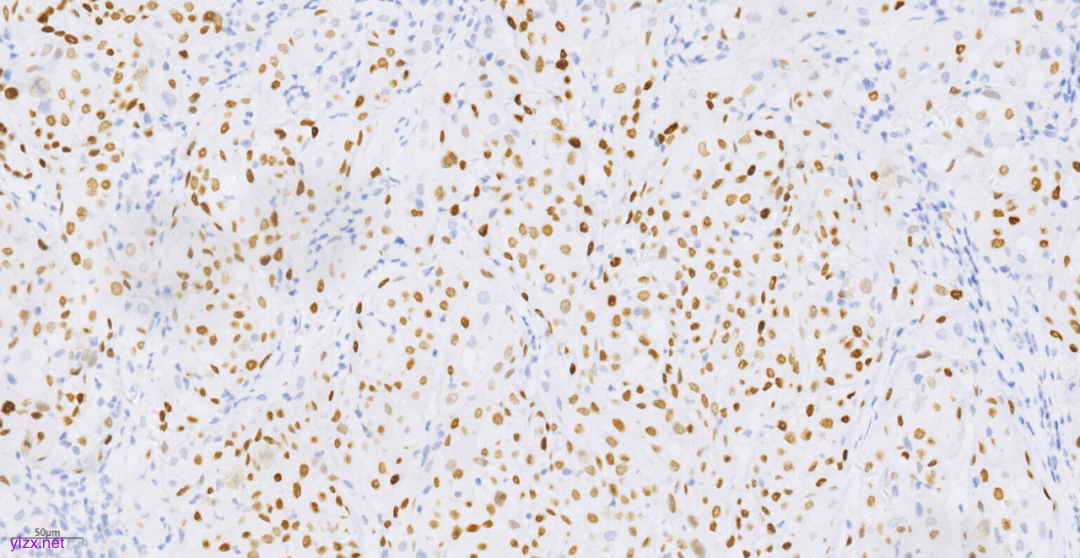

3.3免疫组化(图10-图12):

鳞癌成分CK(+),P40(+),CK5/6(+),p63(+),CK7(-),CK20(-),ER(-),PR(-),WT-1(-),Ki-67(约70%+).

图10 免疫组化示肿瘤细胞P40(+)。

免疫表型:SCC肿瘤细胞CK5/6、p63、p40阳性,ER、PR阴性。